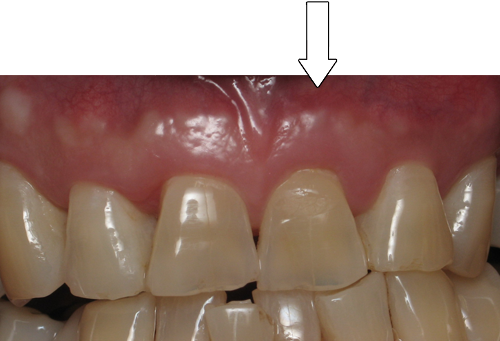

Smile Gallery

Orthodontic Treatment X-ray - Before

After Series of Teeth Extractions, Upper Left Canine Unerupted.

Ready to Start Ortho Treatment